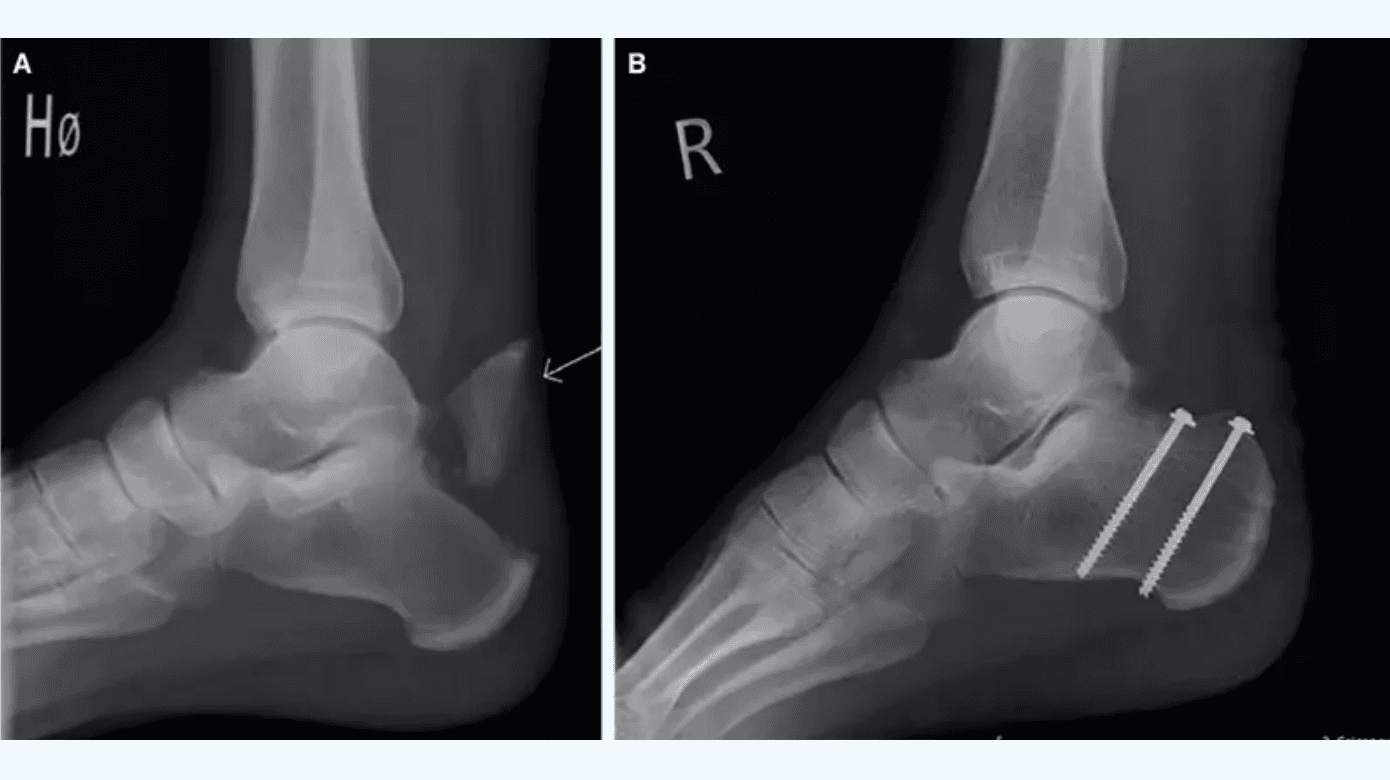

En 71-årig mand henvendte sig i skadestuen to dage efter et mindre vrid i foden ved et fald ned ad få trappetrin. Objektivt fandtes udbredt hævelse lokaliseret om ankelleddet. Distalt for akillessenetilhæftningen blev palperet en ossøs defekt på cirka 2 cm ved tuber calcanei samt ossøst materiale på begge sider af defekten med misfarvet og udspændt hud. Thompsons test var positiv med nedsat plantart fleksionsrespons. Der fandtes ingen øvrige positive fund, herunder ingen sideforskel ved Matles test. På mistanke om ossøs akillesseneavulsion blev der foretaget røntgenbillede af calcaneus, der bekræftede fund af den såkaldte andenæbsfraktur (Figur 1).

Patienten fik anlagt Walker-støvle med tre hælkiler uden tilladelse til at støtte på foden med henblik på at approksimere fragmenterne, slække i trækket fra akillessenen og dermed aflaste bløddelene, og dette blev dokumenteret. Patienten blev indlagt og opereret den følgende dag efter fodkirurgisk konference, hvor det afrevne fragment blev fikseret med to kanylerede skruer, washers og fibertape. Postoperativt var patienten uden støtte i fire uger.

Ved postoperativ kontrol fandtes huden hævet og macereret med epidermolyse. Der blev podet fra det eksponerede område og opstartet behandling med profylaktiske antibiotika. I de følgende måneder voksede defekten sig gradvist større, og patienten undergik multiple, mindre bløddelsrevisioner med vacuum-assisted closure (VAC)-behandling og opfølgning på sårcenteret. Der blev konfereret med plastikkirurgisk og mikrobiologisk afdeling med vejledning i videre behandling vedrørende henholdsvis bløddele og antibiotika. Patienten blev senere indlagt og undergik større operation med fjernelse af osteosyntesemateriale og næsten halvdelen af en avital akillessene (Figur 1). Postoperativt blev besluttet kontinuert antibiotikabehandling i tre måneder med videre sårbehandling.

Seks måneder efter traumet havde patienten fortsat en betydende bløddelsdefekt, men var infektions- og smertefri med gangfunktion (Figur 1).